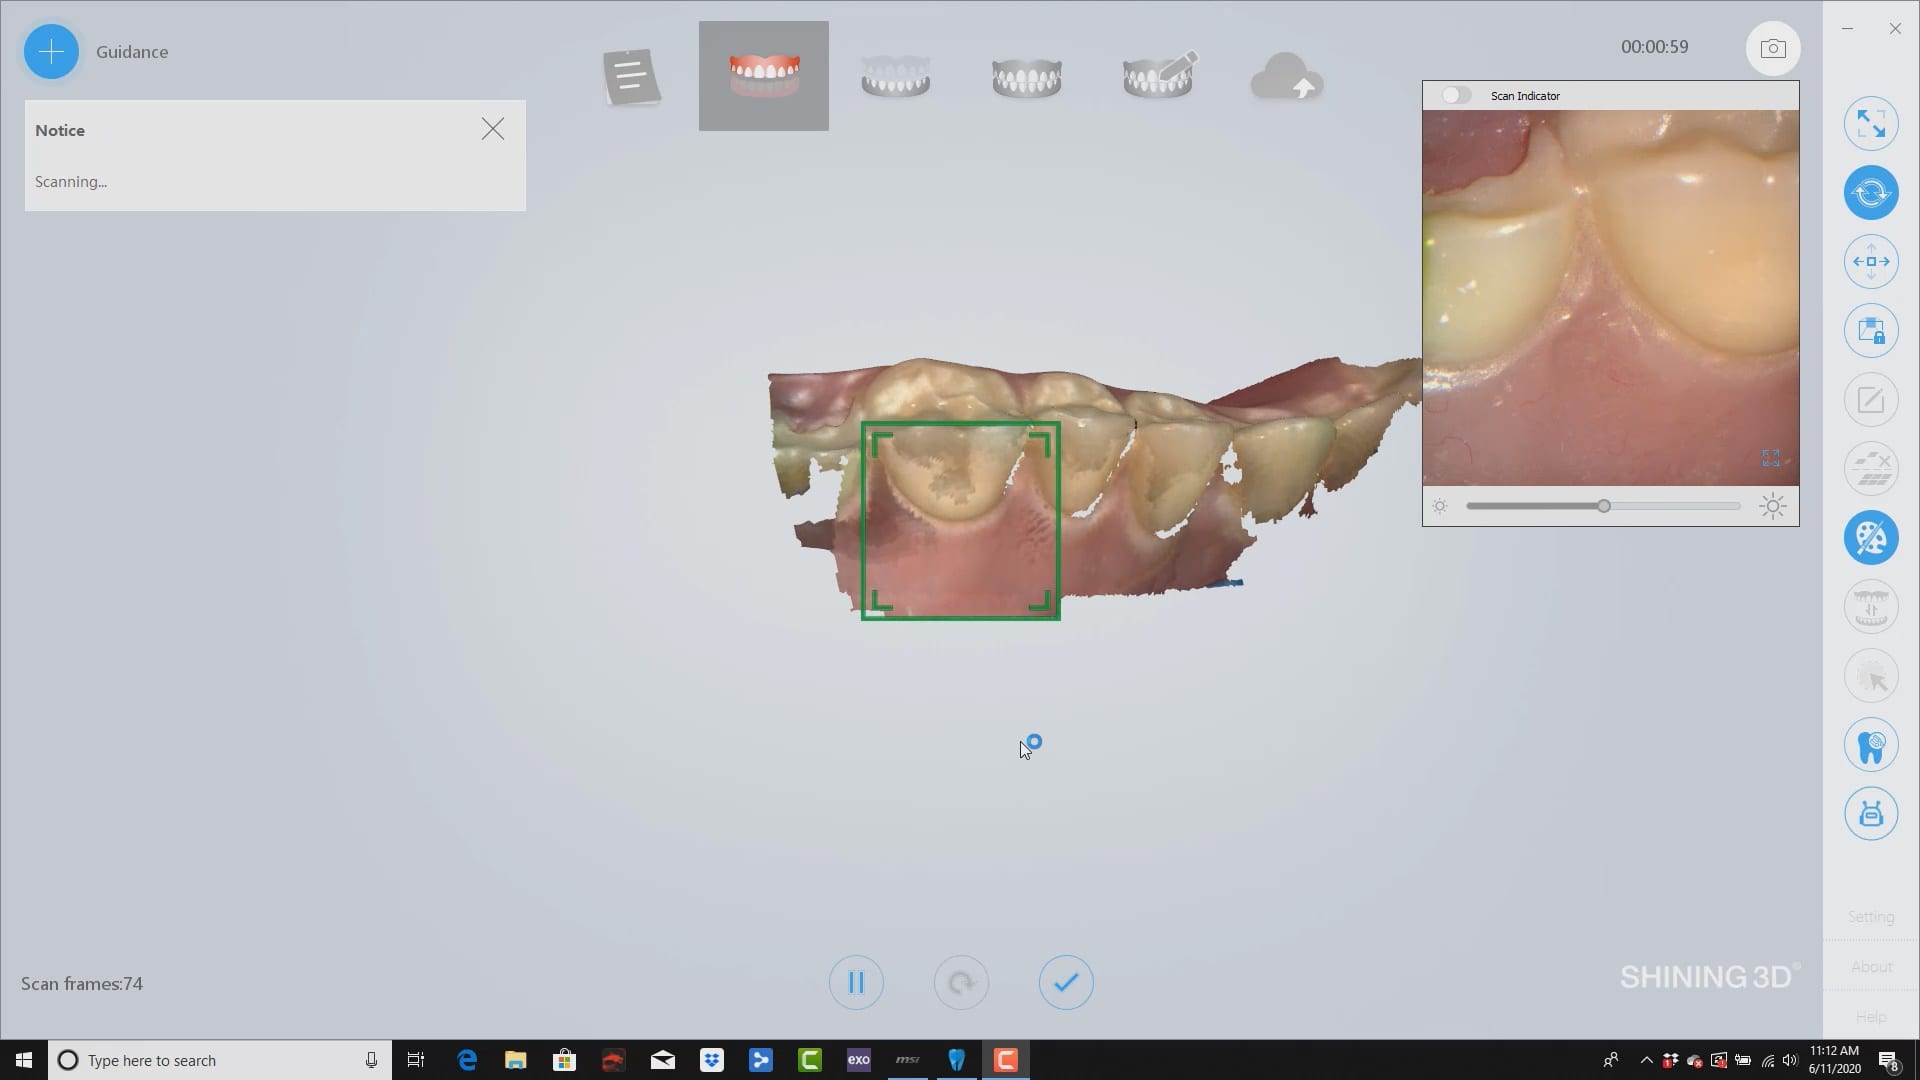

buccal bite taken intra-orally to mount arches at proper vertical dimension. you can see how the camera performs in this challenging case